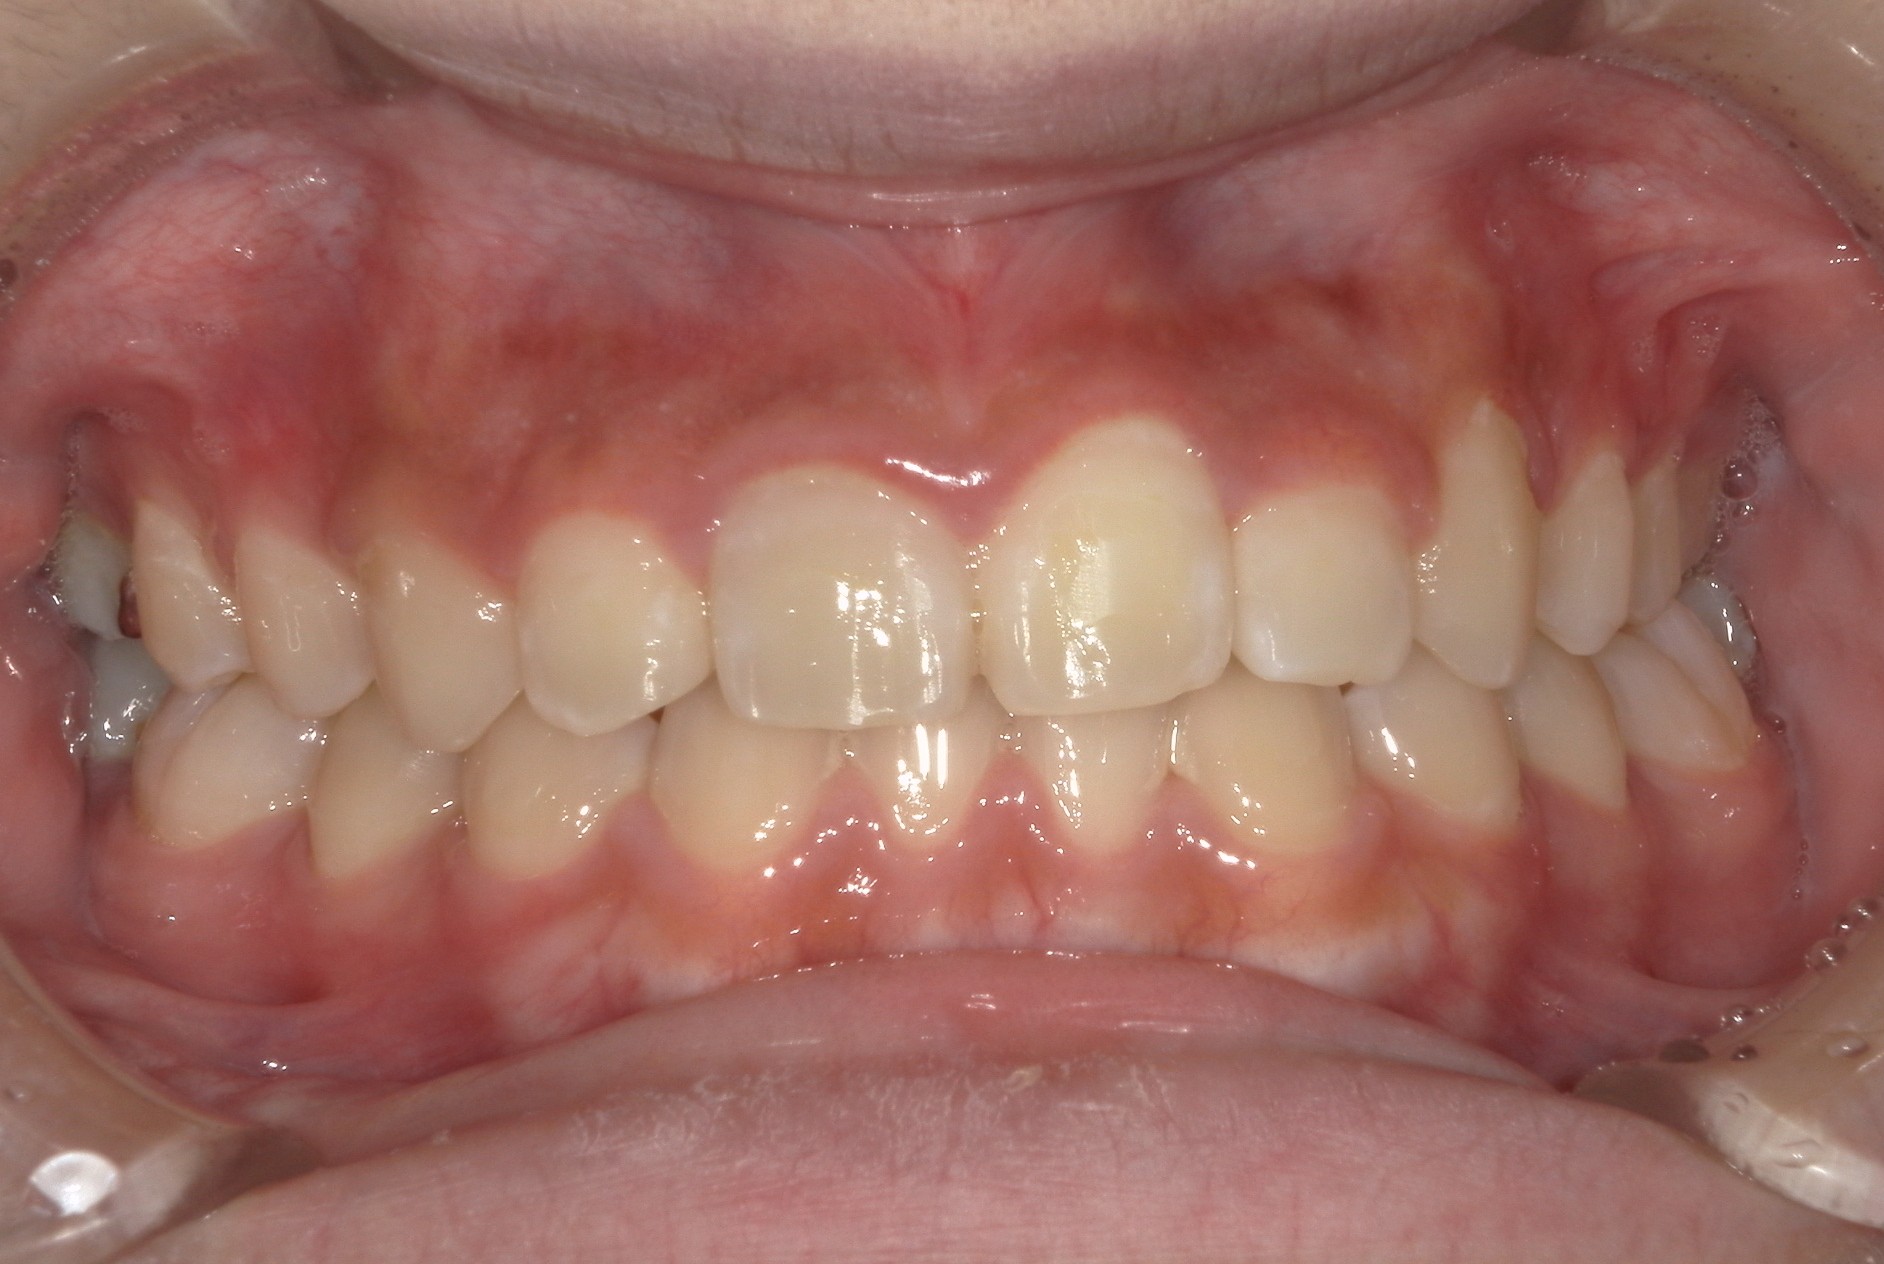

矯正術前:正面

| 主訴 | 上の歯が1本だけ奥に引っ込んでいることが気になる |

| 治療内容 | 患者様は、上の歯が1本だけ奥に引っ込んでいることを気にされており、矯正検査後Ⅱ級傾向の叢生と診断いたしました。ワイヤー矯正後に、インビザラインによる仕上げ矯正を行っております。 |